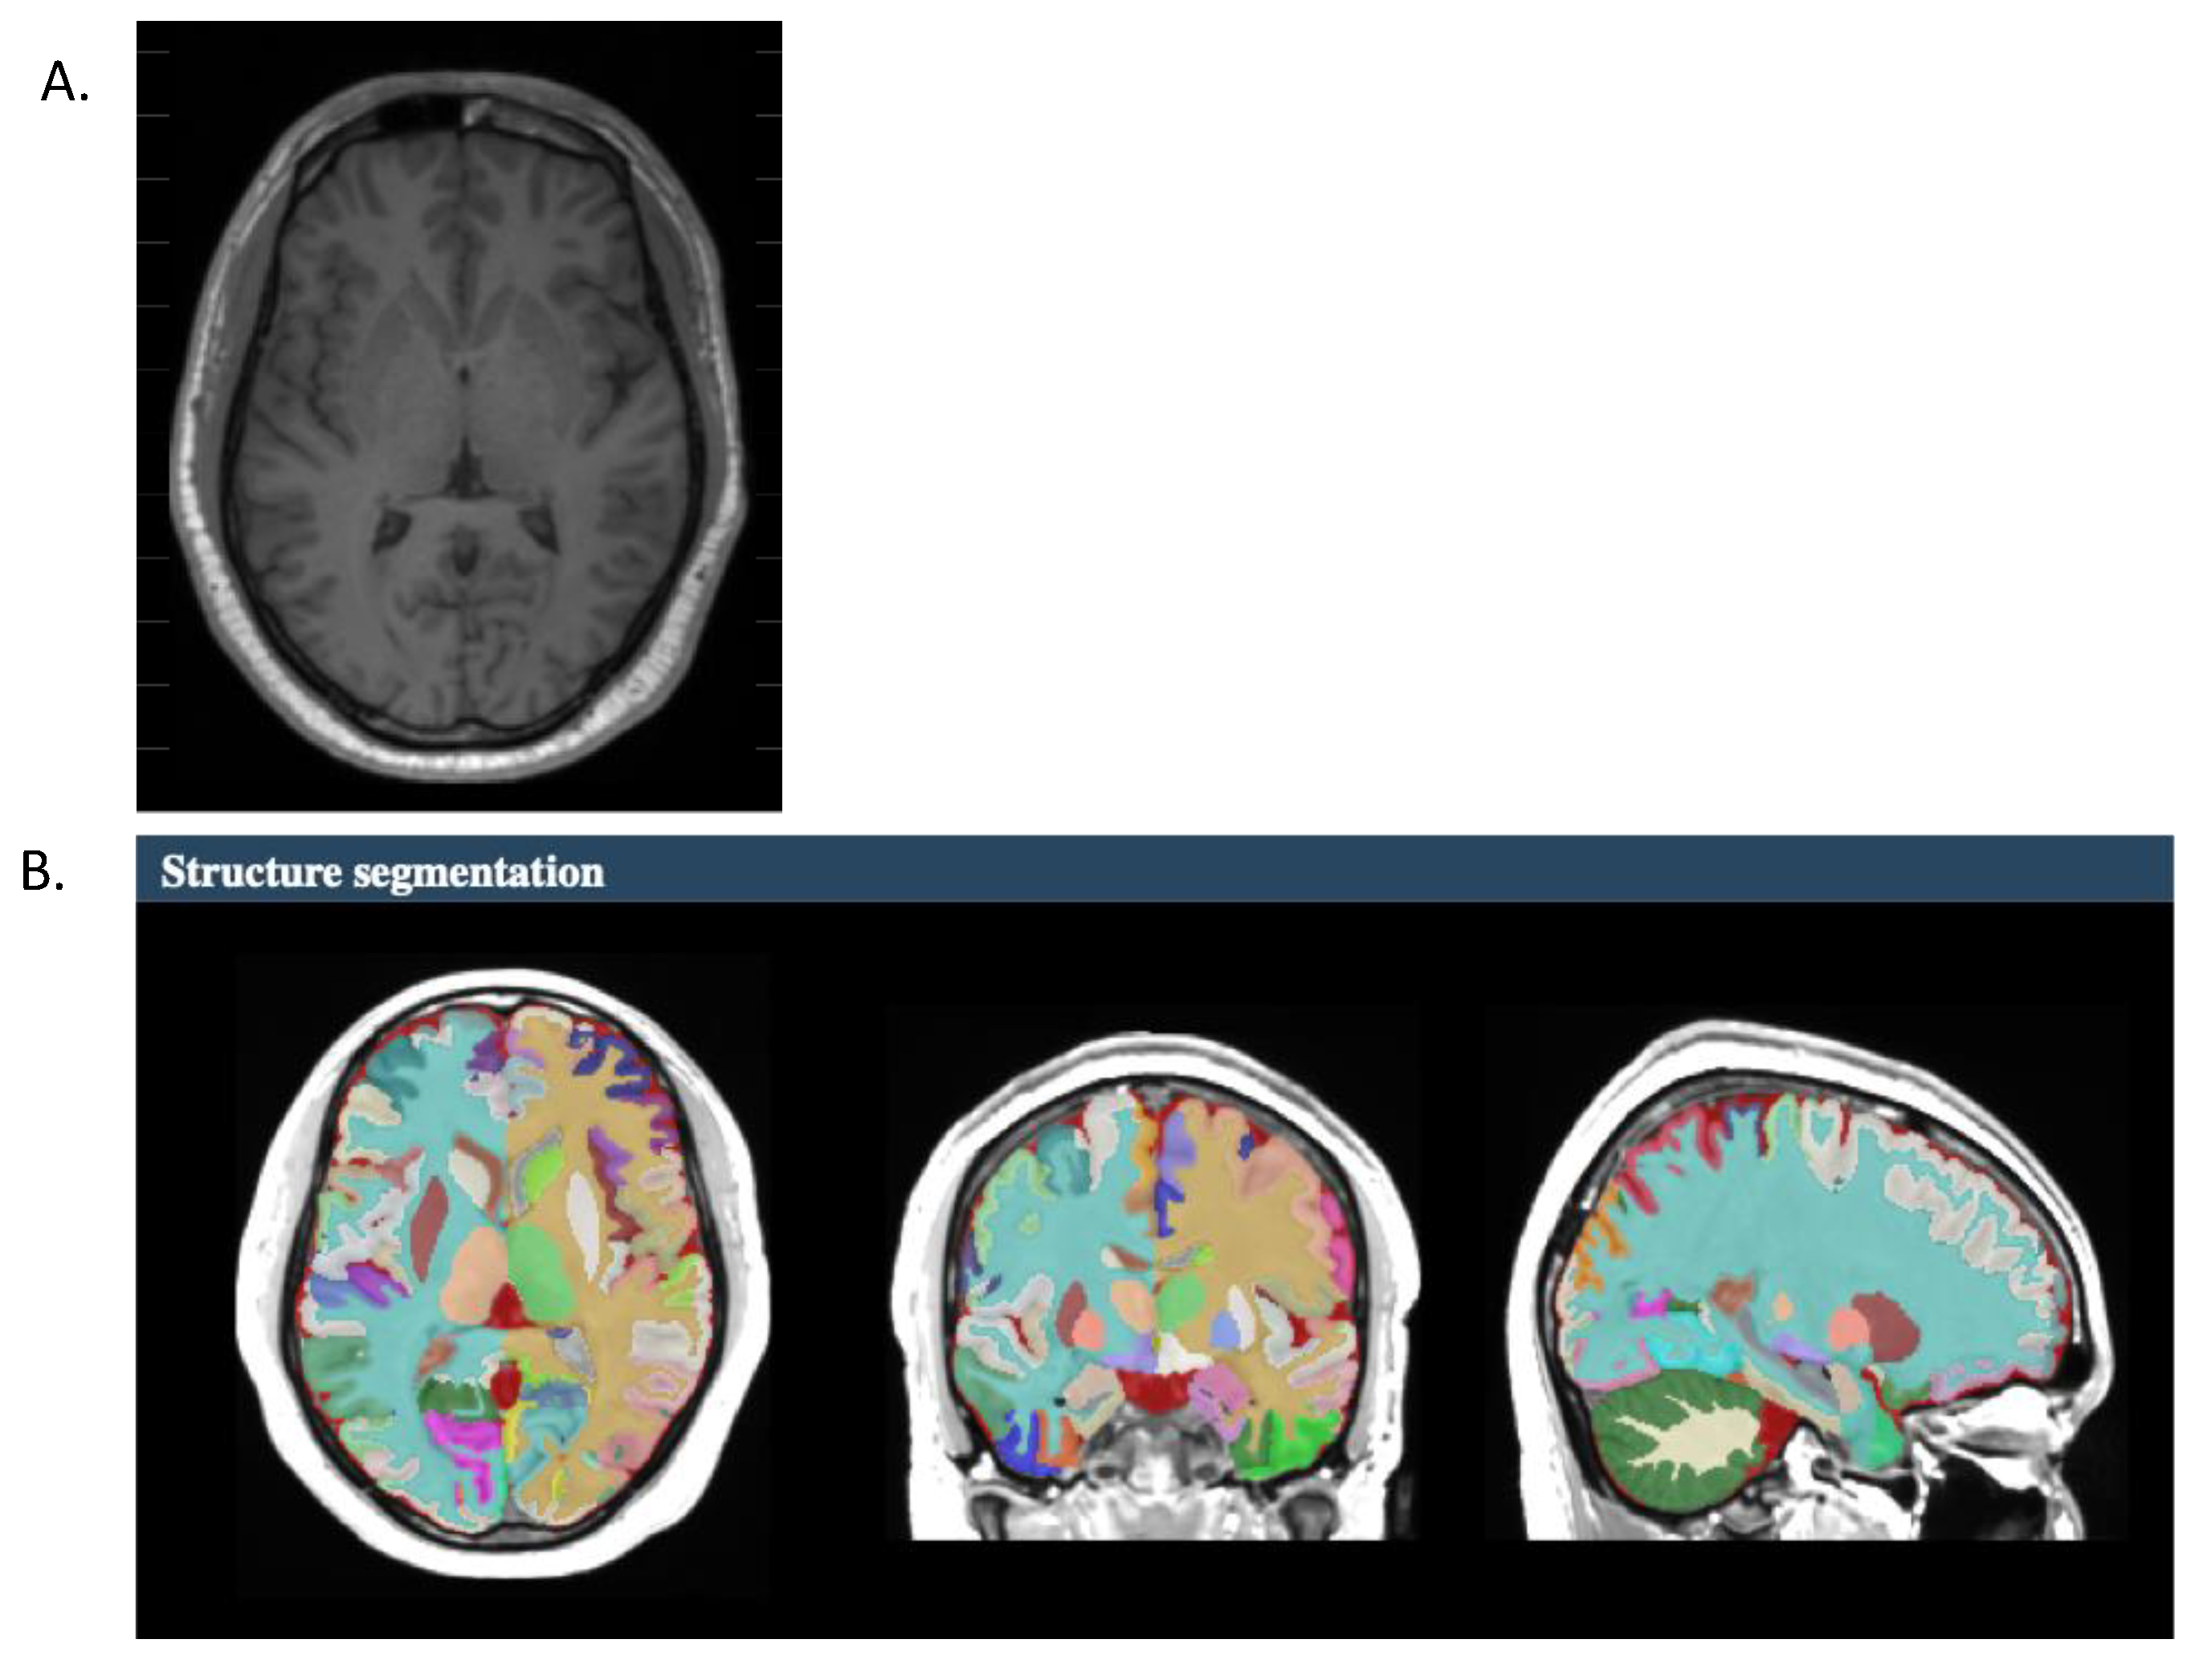

2.3. Segmentation Measurements